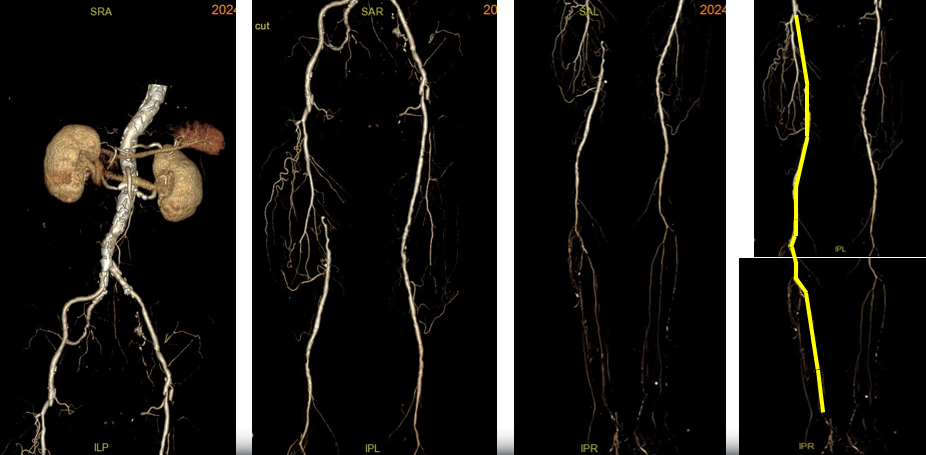

辅助检查:ABI(左0.72,右0.56),下肢动脉彩超显示双下肢动脉硬化伴多发斑块,右侧股浅动脉上段闭塞,双侧胫前动脉中下段接近闭塞。CTA提示:腹主动脉粥样硬化,右侧股动脉、双侧胫前动脉中重度狭窄、闭塞,左侧股动脉、双侧腓动脉、胫后动脉轻度狭窄,左侧髂内动脉局限性闭塞。

术前CTA

手术方案

根据PLAN评估体系,本例患者TAP为开通股浅动脉。